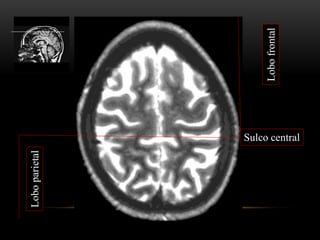

Lobofrontal

Loboparietal

Sulco central